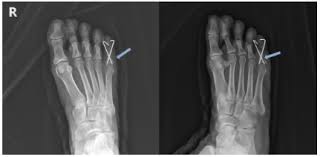

또한, 복합 골절이나 압박 골절과 같이 더 복잡한 경우에는 수술이 필요할 수 있으며, 뼈가 조각나거나 비스듬하게 부러진 경우에는 금속판을 추가적으로 사용할 수 있습니다.

- 압박골절로 조각이 많이 발생한 경우: 많은 골조각이 발생한 경우, 수술을 통해 정확한 정렬과 고정이 필요합니다.